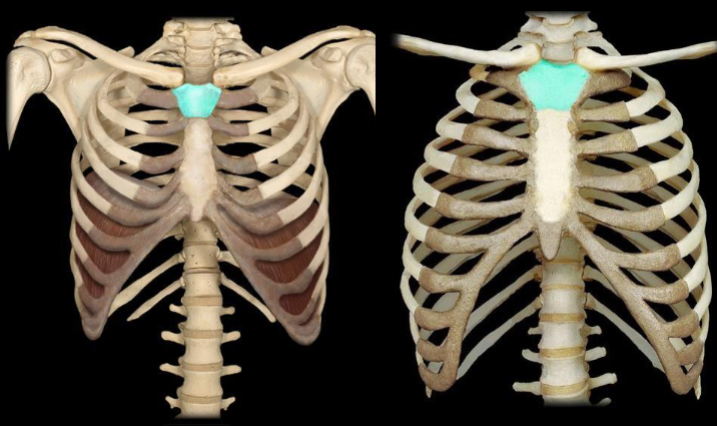

What bone is highlighted in this image?

rib cage (thoracic cage)

What type of ribs are highlighted in this image?

vertebral (false, floating) ribs (the two bottom ribs in the back)

What type of ribs are highlighted in this image?

vertebronchondral (false) ribs (the 3 ribs right above floating)

What type of ribs are highlighted in this image?

vertebrosternal (true) ribs (the spiral looking bones going from behind to the front)